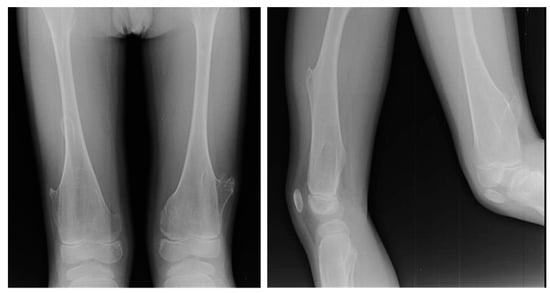

Figure 3. X-rays of a 10-year-old patient affected by Ollier syndrome.

In both diseases, there is a higher risk of malignant transformation in chondrosarcoma (40%) [81]; in detail, the risk is 35% higher in Ollier disease and 50% higher in Maffucci syndrome. Histological features of both conditions include hypercellularity and cellular atypia (Figure 3).